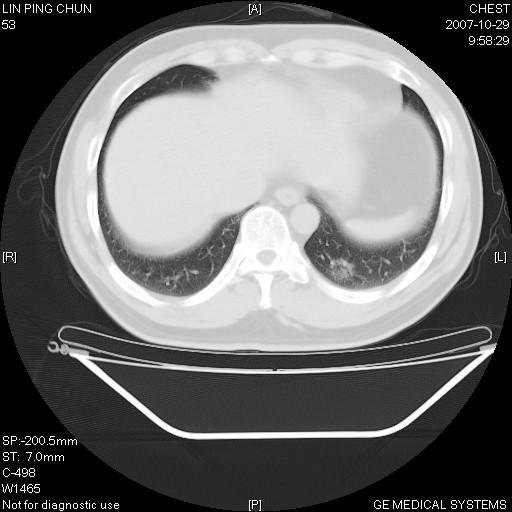

标题: CT10239:男,42Y.我自己的胸部CT扫描,今天10点突然咯血一次。

我自己胸部ct扫描,求助大家,我自己还不能给自己诊断。其他层面纵隔窗无异常。

补充:男,42y.今天10点突然咯血一次。余无异常。

谢谢大家!!!上传纵隔窗,请大家帮我分析。

左下肺后基底段磨玻璃样影,很多病都可以。不能吊以轻心。应该做局部增强hrct进一步检查,并严格抗炎治疗后复查或经皮活检。

左下肺后基底段小斑片泪膜玻璃样影,其内可见空泡影,边缘可见小毛刺影。建议抗炎治疗复查,肿瘤待排